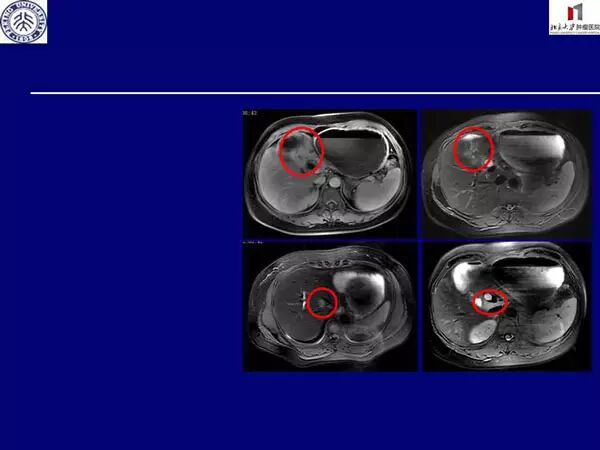

患者42岁,女性,因“间断下腹痛1年,腹胀伴呃逆9个月”至我院就诊。患者1年前(2014年5月)因腹痛在当地体检,发现CA199升高至298.8 U/ml,胃镜及CT检查未见异常。2014年8月出现上腹饱胀,进食后加重,伴呃逆,食欲下降,再次胃镜检查示:幽门口变形、肿胀、狭窄,表面糜烂,质地脆,易出血,十二指肠球部充血肿胀,活检病理提示:低分化腺癌。 病理会诊示:(胃活检)黏膜组织内见小灶中分化腺癌,Lauran 肠型, HER-2(2+)FISH(-)CA199>1000 U/ml。腹部MRI示:胃窦部胃壁增厚,符合Borrmann 3型胃癌征象(T4b),侵犯肝左叶伴肝内胆管扩张。肝多发长T2信号灶,转移不除外。胃周及腹膜后多发肿大淋巴结,考虑转移(图1)。

图1.腹部MRI所示